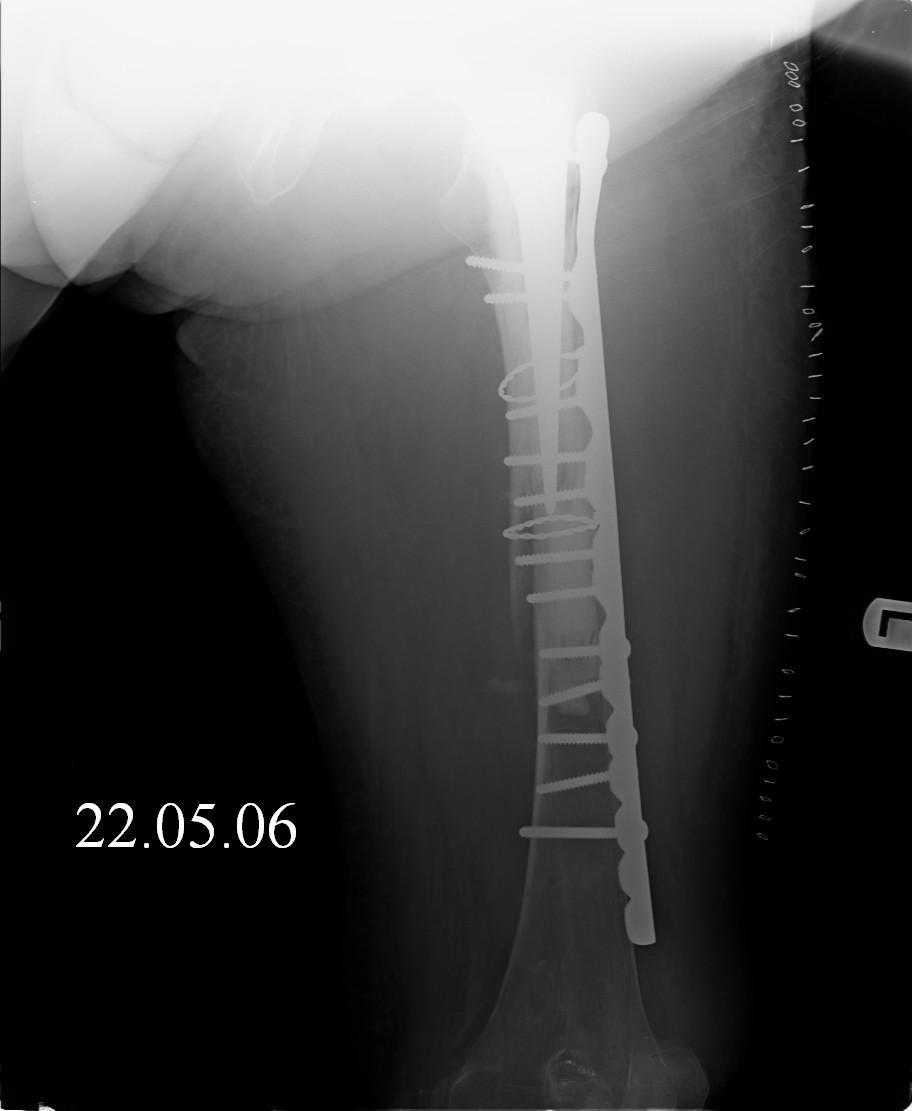

Hello! This is just illustration in one of the choice of treatment